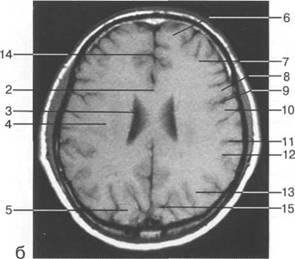

теменно-затылочная борозда; 11 - семиовальные

мие; 26 - поясная борозда; 27 - головка хвостатого ядра; 28 - бледный шар; 29 - височный рог боково

цистерна четверохолмия; 14 -прямой синус; 15 -лобный рог; 16 - головка хвостатого ядра; 17 -перед